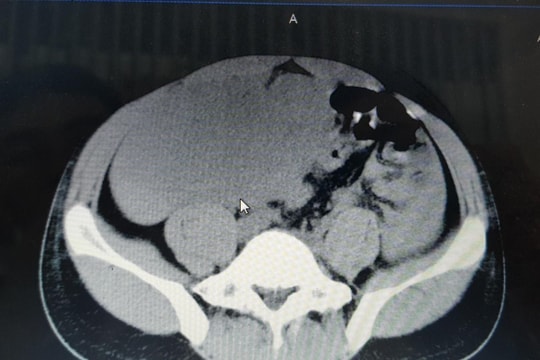

韩国库东综合医院:成功为一名14岁女孩切除巨大卵巢生殖细胞肿瘤

韩国库东综合医院外科的医生们刚刚成功实施了一项手术,将患者右侧卵巢内一个大小达 18 x 9 x 29 厘米的肿瘤分离并完全切除……

义安妇幼医院采用现代腹腔镜手术切除了一个巨大的子宫肌瘤。

义安妇幼医院妇儿科的医生们刚刚成功地通过腹腔镜手术切除了一个巨大的子宫肌瘤(相当于怀孕4个月的体积)……

一名21岁女孩腹部异常增大,意外发现一个球状肿瘤。

July 8, 2020 07:25

(Baonghean.vn)——近日,荣市国际医院的医生成功地为一名PTTH患者(21岁)进行了手术,该患者左侧卵巢囊肿几乎占据了整个腹部。

荣市综合医院成功为一名患有罕见肠系膜肿瘤的 29 岁患者实施了手术。

August 23, 2019 15:27

(Baonghean.vn)——近日,荣市综合医院为荣市患者 Tran Van H(29 岁)实施了肠系膜巨大肿瘤切除手术。